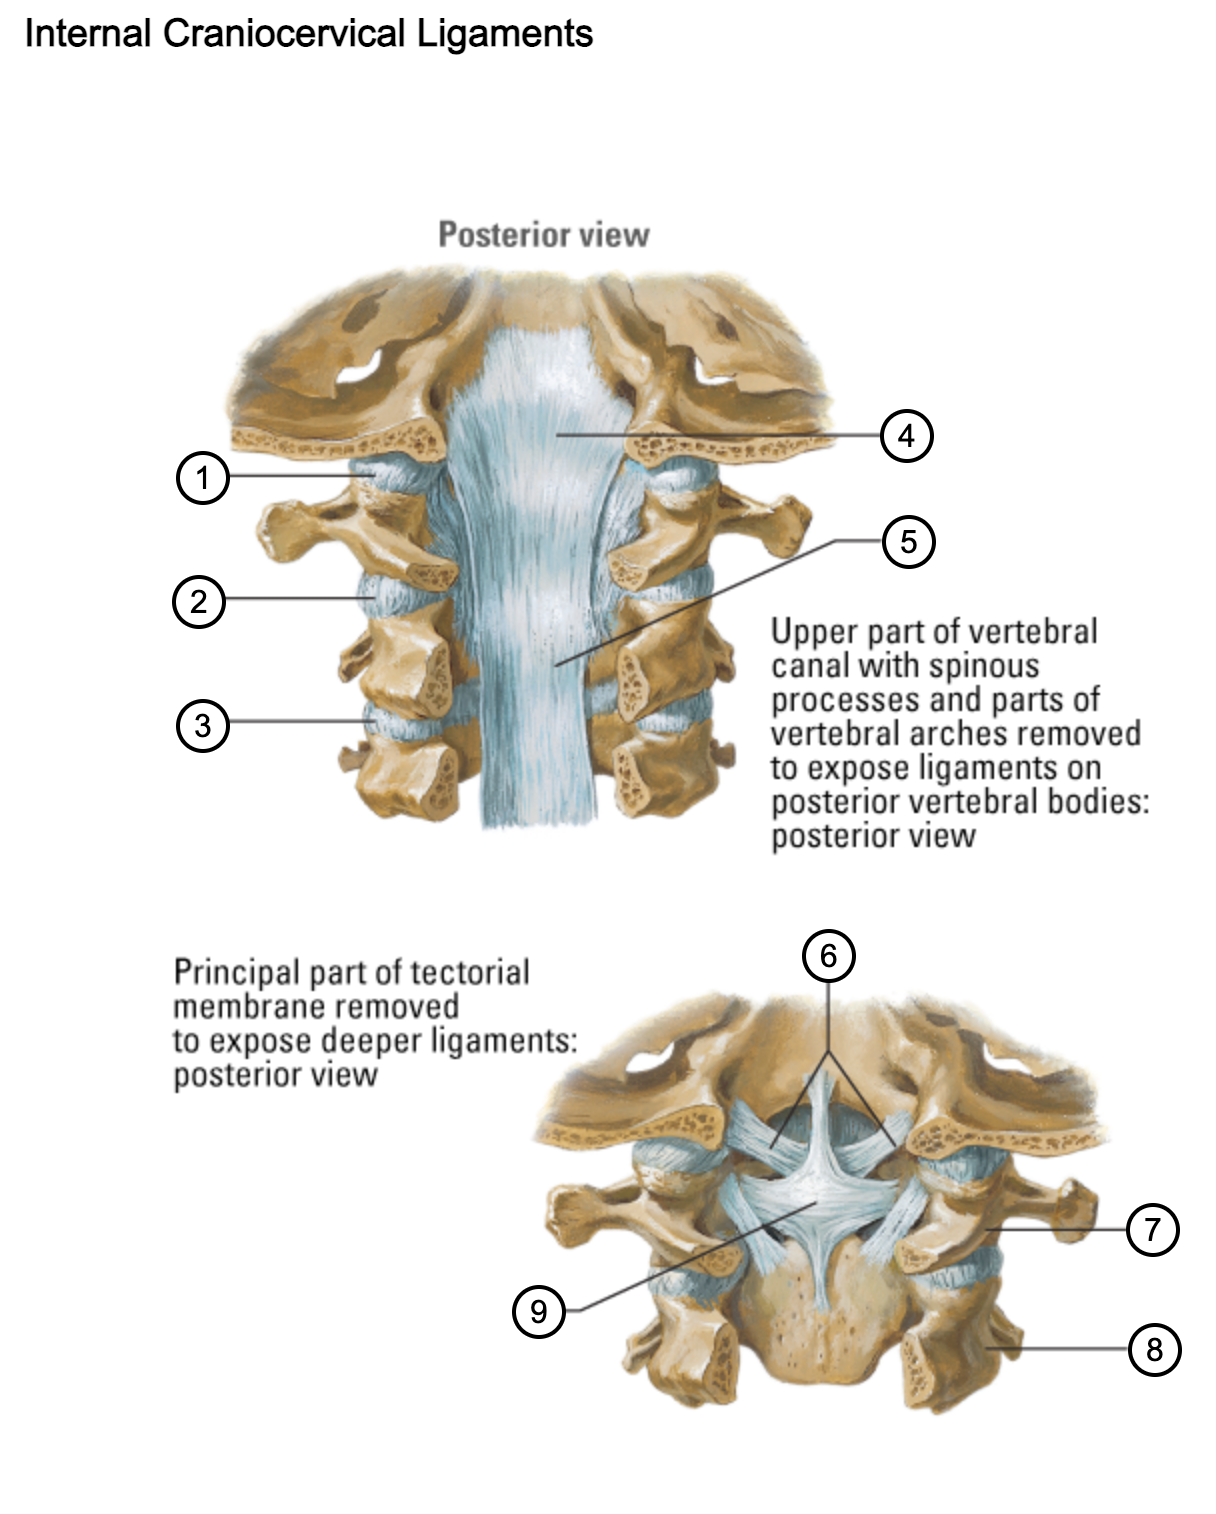

1

capsule of atlantooccipital joint

2

capsule of lateral atlantoaxial joint

3

capsule of zygapophysial joint (between axis and C3 vertebra)

4

tectorial membrane of cervical vertebral column

5

posterior longitudinal ligament

6

alar ligaments

7

atlas (C1)

8

axis (C2)

9

cruciform ligament (superior longitudinal band; transverse ligament of atlas; inferior longitudinal band)